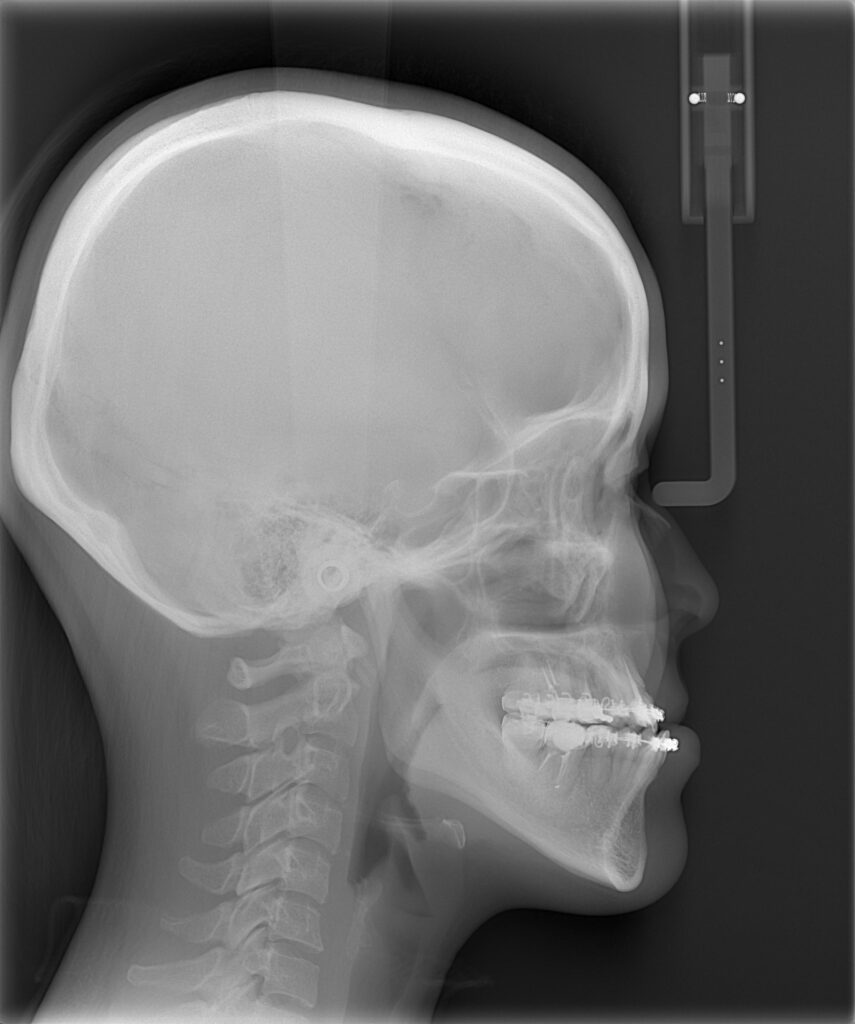

レントゲンを用いて骨格の特徴を把握します。白線の輪郭は標準的な骨格を表しています。標準骨格と比べると、下顎が前に出ていて、なおかつ垂直方向に長いことがわかりました。